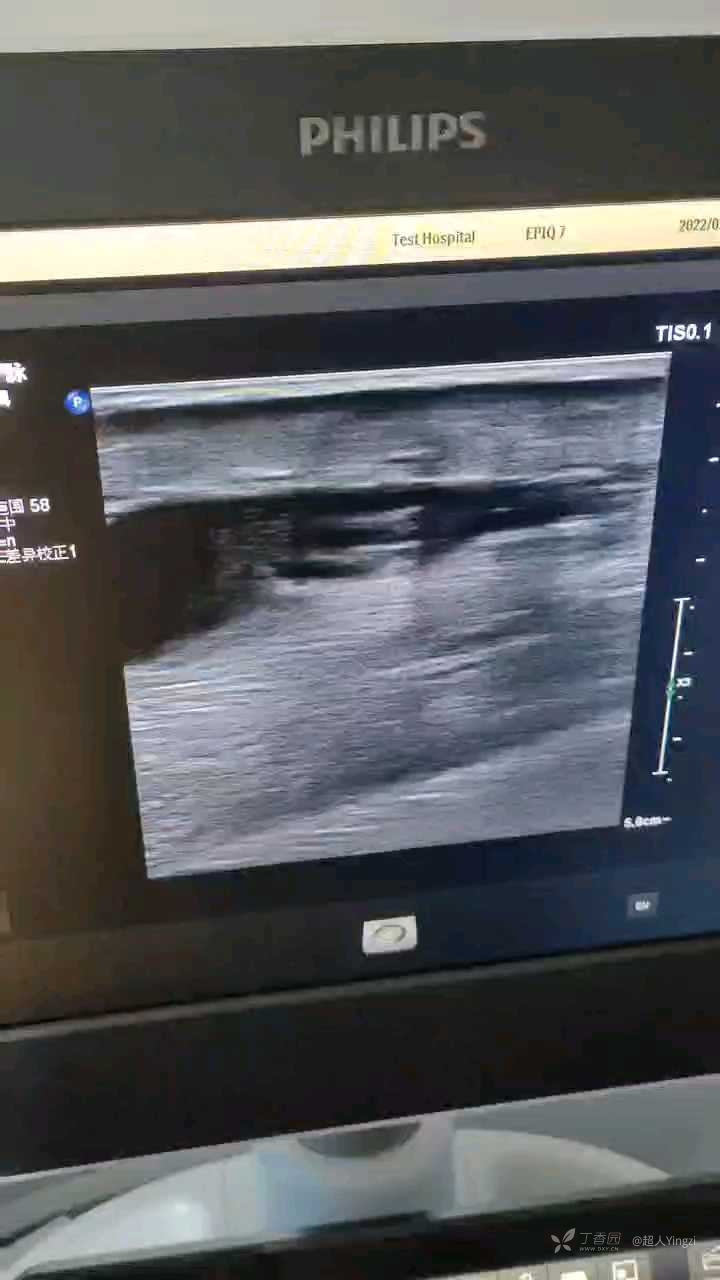

患者女70岁,于无外伤病史,左下肢小腿疼三个月,最近肿,来就诊

左小腿内侧,小腿中段到近腘窝处